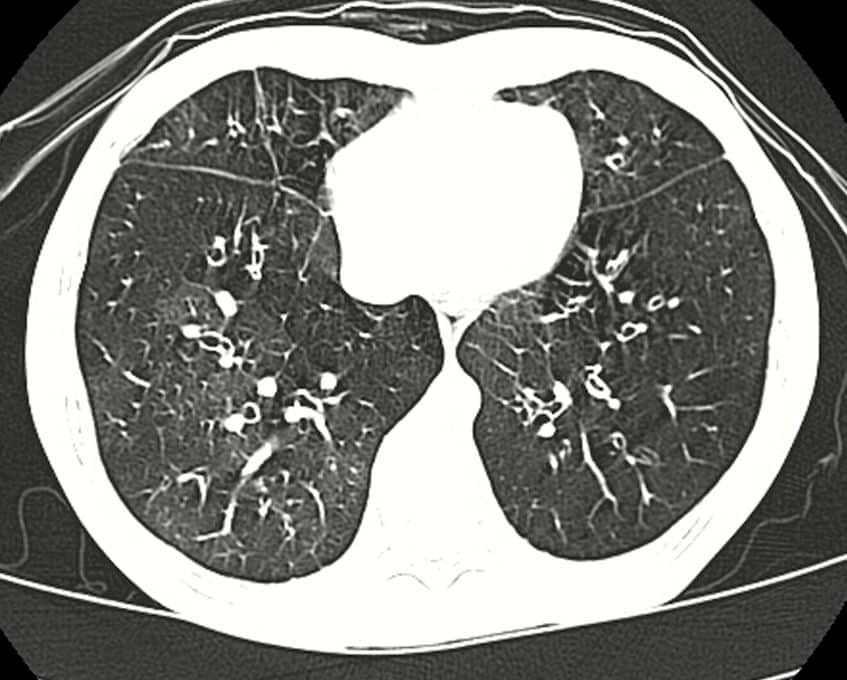

Entre os sintomas mais comuns da bronquiolite obliterante estão tosse seca persistente, chiado no peito, falta de ar progressiva e cansaço intenso mesmo com pequenos esforços. Exames de função pulmonar costumam mostrar redução do volume expiratório e limitação fixa no fluxo de ar. Tomografias podem revelar alterações típicas e, em casos mais graves, o transplante de pulmão pode ser a única opção terapêutica.